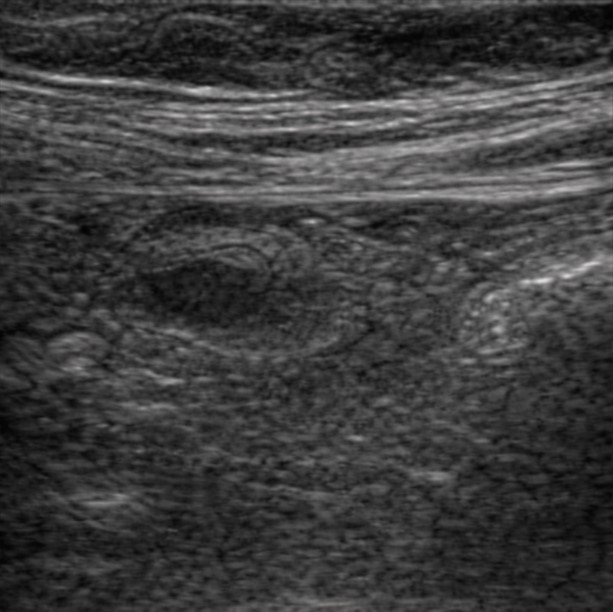

[362,Gastrointestinal [GI]] 40/F,Right lower quadrant pain

Gastrointestinal [GI]

US,

What is the most likely diagnosis?

Acute appendicitis

Cecal diverticulitis

Epiploic appendagitis

Omental infarction

Crohn disease